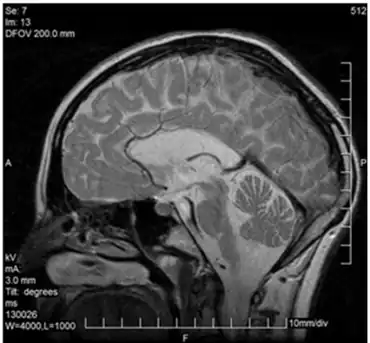

MRI

The MRI of patients with VWM shows a well defined leukodystrophy. These MRIs display reversal of signal intensity of the white matter in the brain. Recovery sequences and holes in the white matter are also visible.[4] Over time, the MRI is excellent at showing rarefaction and cystic degeneration of the white matter as it is replaced by fluid. To show this change, displaying white matter as a high signal (T2-weighted), proton density, and Fluid attenuated inversion recovery (FLAIR) images are the best approach. T2-weighted images also displaying cerebrospinal fluid and rarefied/cystic white matter. To view the remaining tissue, and get perspective on the damage done (also helpful in determining the rate of deterioration) (T1-weighted), proton density, and FLAIR images are ideal as they show radiating stripe patterns in the degenerating white matter. A failure of MRI images is their ineffectiveness and difficulty in interpretation in infants since the brain has not fully developed yet. Though some patterns and signs may be visible, it is still difficult to conclusively diagnose. This often leads to misdiagnosis in infants particularly if the MRI results in equivocal patterns or because of the high water content in infants' brains. The easiest way to fix this problem is a follow-up MRI in the following weeks. A potentially similar appearance of MRI with white matter abnormalities and cystic changes may be seen in some patients with hypomelanosis of Ito, some forms of Lowe's (oculocerebrorenal) disease, or some of the mucopolysaccharidoses.[2]